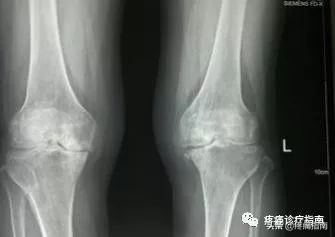

8.影像检查

X线摄片为骨性关节炎的常规检查,早期多正常,中晚期可见关节间隙不对称狭窄,关节面下骨硬化和变形,关节边缘骨赘形成及关节面下囊肿和关节腔游离体。根据Kellgren和Lawrecne的放射学诊断标准,骨性关节炎分为5级。0级正常。I级关节间隙可疑变窄,可能有骨赘。II级有明显的骨赘,关节间隙轻度变窄。III级中等量骨赘,关节间隙变窄较明确,软骨下骨质轻度硬化改变,范围较小。IV级大量骨赘形成,可波及软骨面,关节间隙明显变窄,硬化改变极为明显,关节肥大及明显畸形。

☝5度骨性关节炎